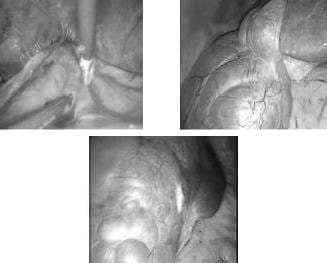

Se trata de una paciente de 53 años con enfermedad de inicio insidioso y tres años de evolución, caracterizada por dolor abdominal superior acompañado de distensión posprandial y síntomas de gastritis que, al cabo de unos meses, se acompañó de crecimiento del perímetro abdominal con palpación de masa por parte de la misma paciente, lo que motivó la consulta al médico. Al realizar una TC (figura 1) se observaron múltiples quistes hepáticos (clasificación de Gigot tipo I) y quistes renales, sin alteración de la función renal.

FIGURA 1. Imágenes de poliquistosis hepática.